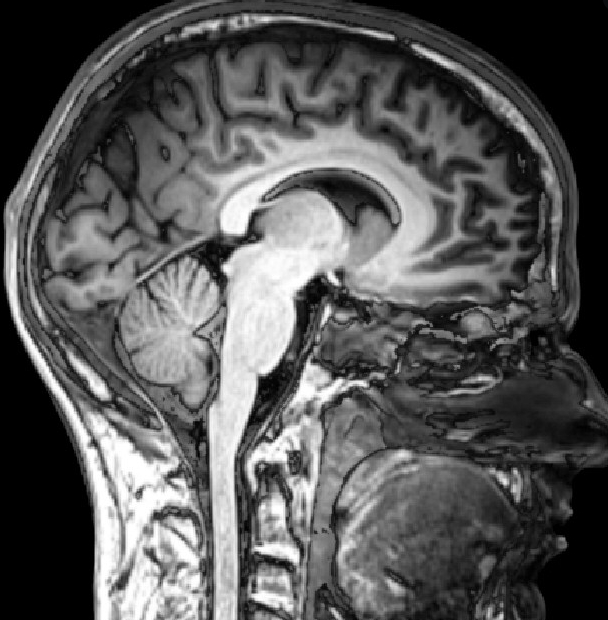

방사선, X-ray를 이용하는 것이 아니라 자기장과 컴퓨터 시스템 및 전파를 결합시켜서 CT 촬영보다 더 신체를 명확하고 분명하게 촬영해 고해상도 단면 영상을 만들어 낼 수 있습니다. 사람의 몸을 3차원으로 볼 수 있습니다.

CT MRI 촬영 차이점 중 큰 부분은 CT 촬영으로는 사람의 몸을 가로면으로 촬영할 수 있는데 MRI 촬영으로는 가로면과 세로면을 모두 촬영할 수 있어 좀 더 자세하고 세밀한 촬영이 가능하기 때문에 CT 촬영한 후 정확한 원인을 알 수 없거나 해서 더 자세히 봐야 할 경우 MRI 촬영을 하게 되기도 합니다.

또한 CT 촬영은 가로단면으로 촬영하기 때문에 복부 촬영에 좀 더 좋은 편이고 MRI 촬영 경우는 가로세로 함께 볼 수 있는 척추나 뇌신경계 촬영에 좀 더 좋습니다.